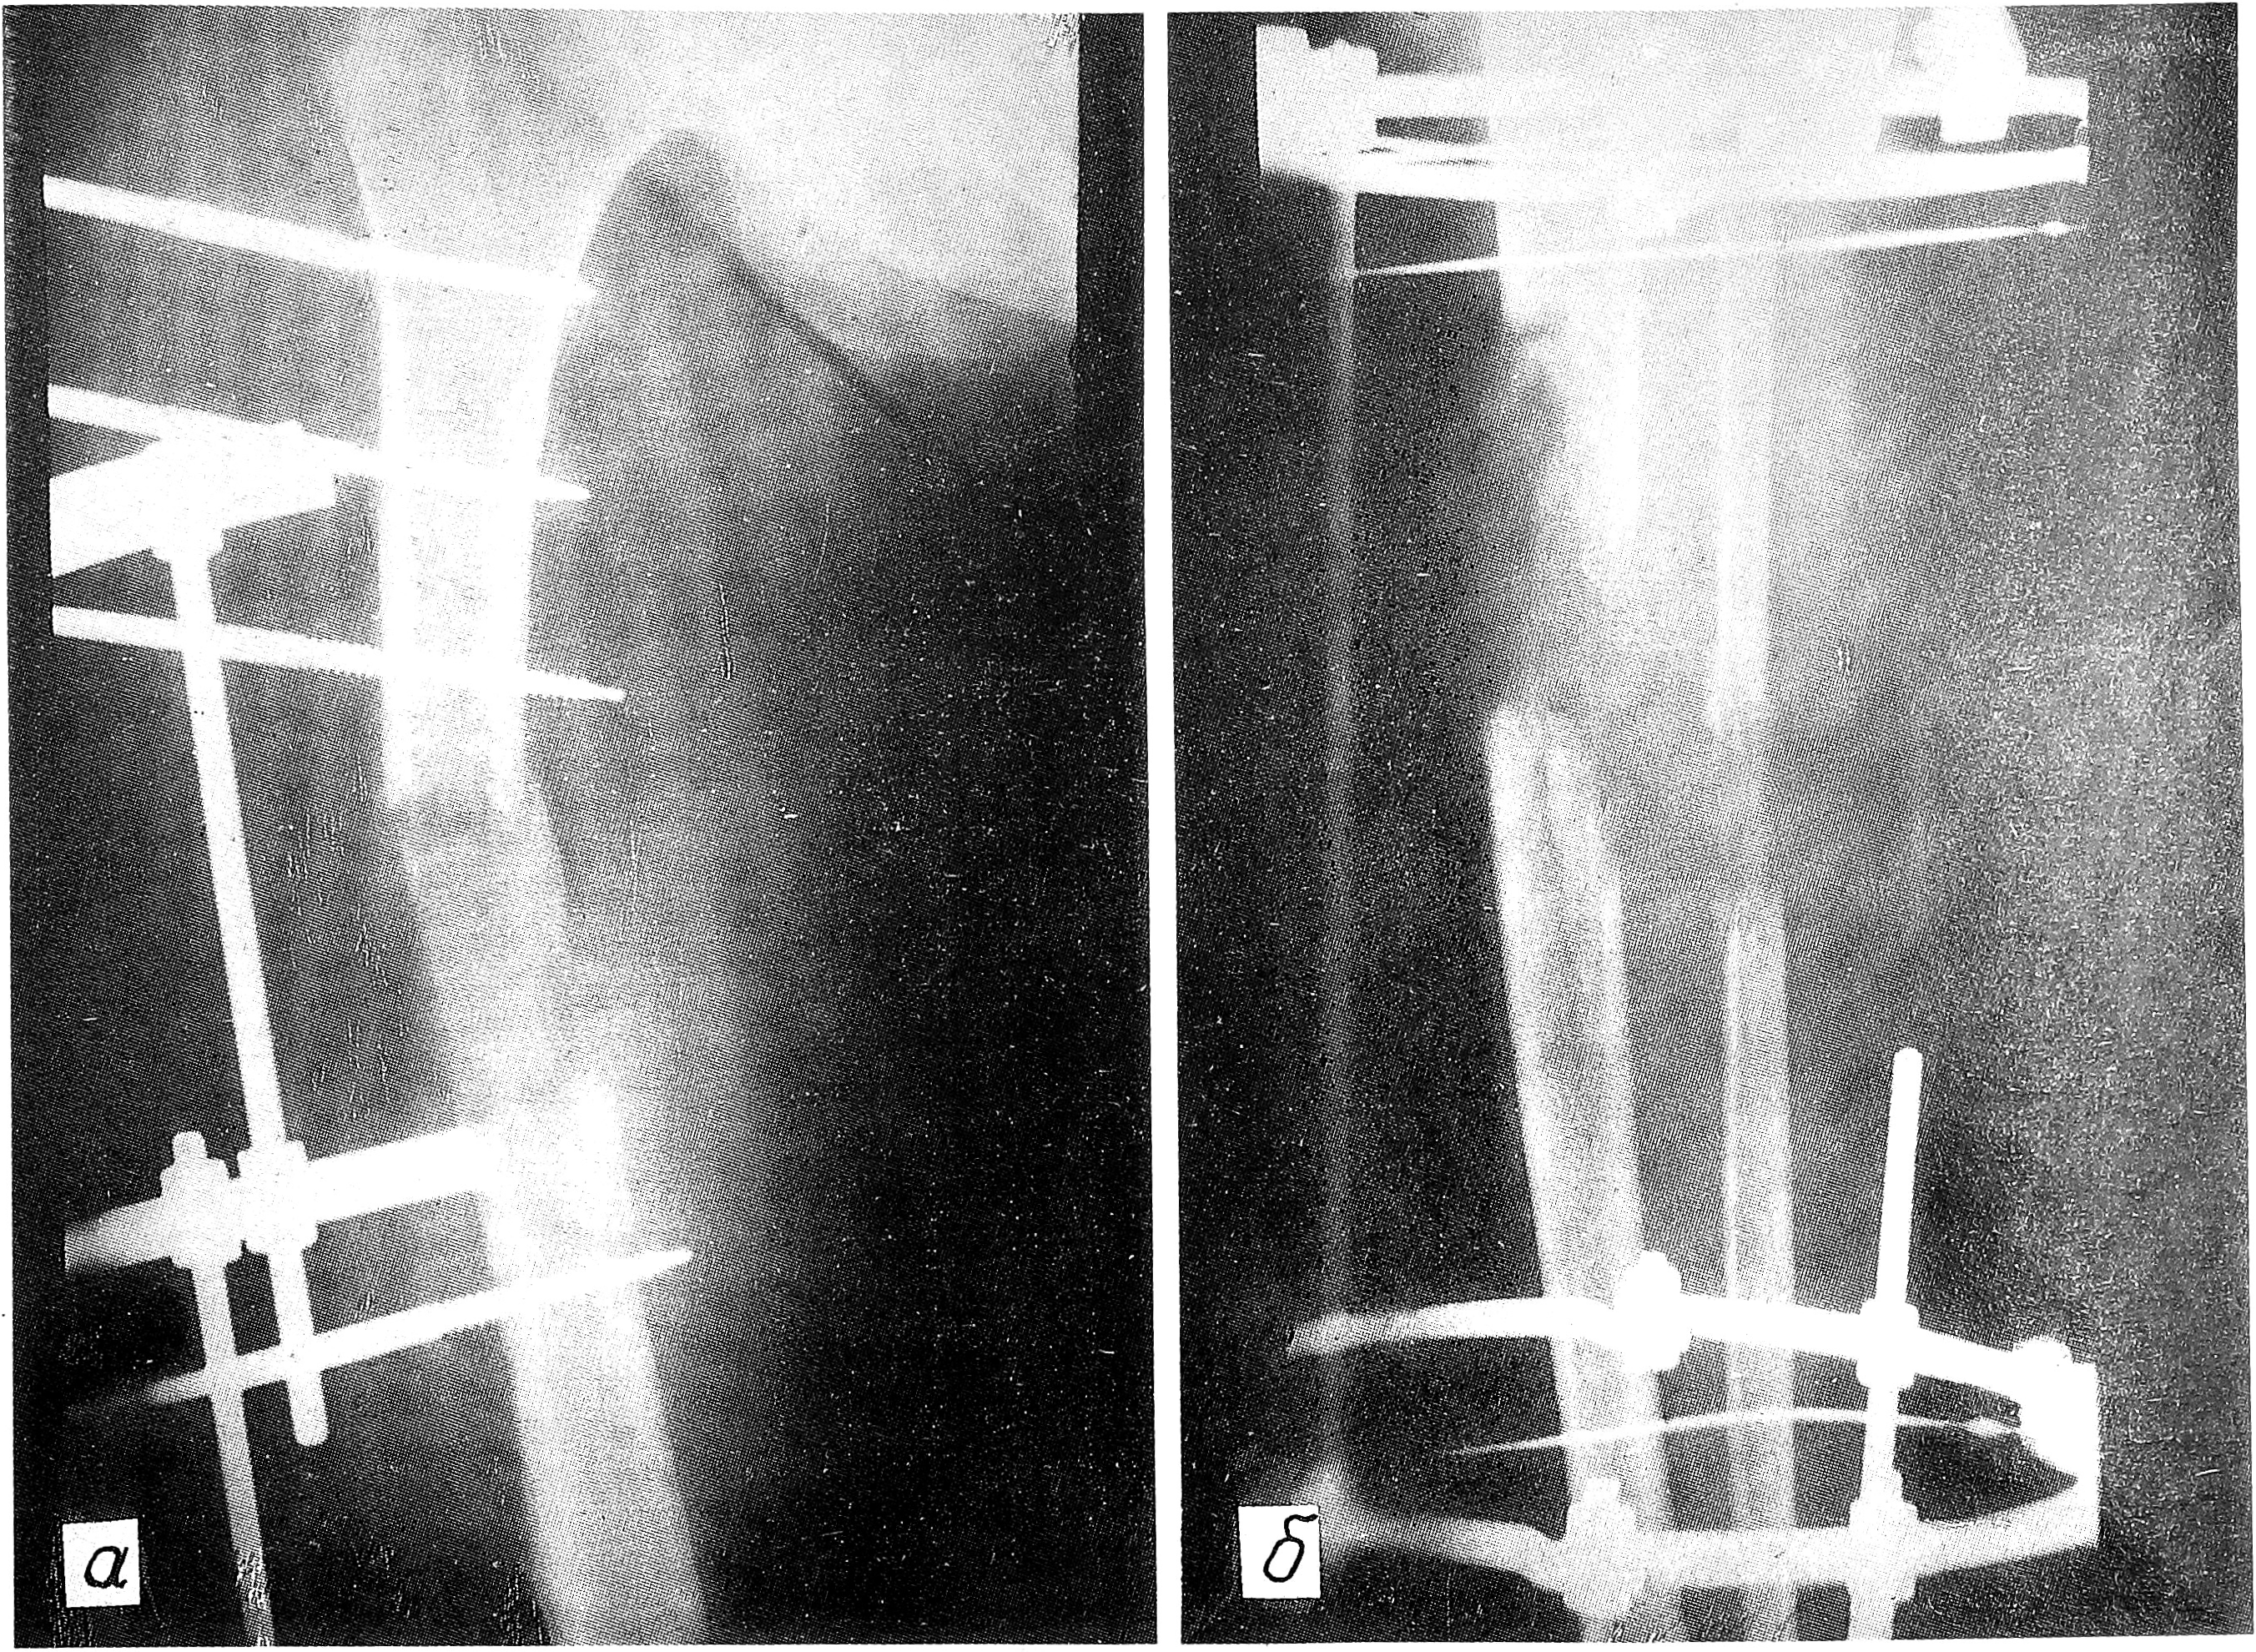

Больная III., 39 лет, поступила 5.01.92. В конце 1990 г. у нее была выявлена деструкция дистального метаэпифиза правой бедренной кости. В одной из областных больниц процесс ошибочно расценен как сосудистая доброкачественная опухоль и 7.05.91 произведена краевая резекция, а 7.10.91 у больной произошел патологический перелом бедренной кости. При обследовании в Московской городской онкологической больнице №62 диагностирована злокачественная фиброзная гистиоцитома (верифицирована морфологически). Коленный сустав резко утолщен за счет опухолевого образования, занимающего переднюю, внутреннюю н наружную поверхности бедра. Paзмер опухоли 25x20 см. На рентгенограммах определяется литический очаг деструкции, занимающий весь дистальный метаэпифиз бедренной кости и распространяющийся на диафиз. Корковый слой истончен и местами разрушен. Перелом медиального мыщелка. На уровне нижней трети бедра — мягкотканный компонент по переднемедиальной поверхности (см. рис. 1 на вклейке).

Рис. 1. Рентгенограмма больной Ш. до операции.

Консолидация костных фрагментов наступила через 3 мес (см. рис. 2 на вклейке). Аппарат был снят и наложена гипсовая лонгета.

Рис. 2. Рентгенограмма той же больной, что на рис.1, через 3 мес после резекции сегмента конечности и иммобилизации в аппарате внешней фиксации.

4.10.92 произведена вторая операция — остеотомия на двух уровнях: в верхней трети бедра и в проксимальном отделе голени. Наложен штифтовой аппарат внешней фиксации и через 2 нед начата дистракция по 1 мм в сутки на двух уровнях. Peгенераты формировались на обоих уровнях. Постепенно у больной развилась эквинусная деформация стопы. 28.09.93 выполнена закрытая ахиллотомия. Через 14 мес достигнуто удлинение конечности на 21 см (14 см на бедре и 7 см на голени). На обоих уровнях сформировались регенераты (см. рис. 3 на вклейке). Аппарат снят и наложена кокситная гипсовая повязка на 2 мес для уплотнения регенератов.

Рис. 3. Рентгенограммы той же больной после остеотомии бедренной кости (а) и костей голени (б) и дистракции в аппарате внешней фиксации. Виден регенерат.